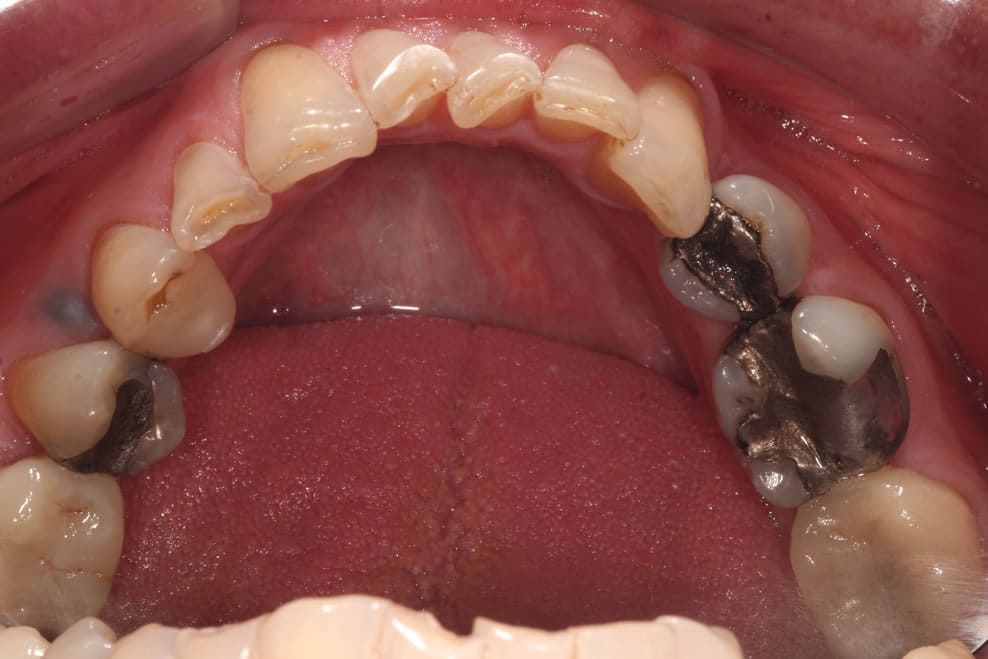

YAY! NO MORE DARK FILLINGS

WHITE FILLINGS

Composite fillings can also be used for cosmetic purposes to restore chipped or uneven front teeth. Many patients also opt to have composite fillings used to replace old, unsightly silver fillings.